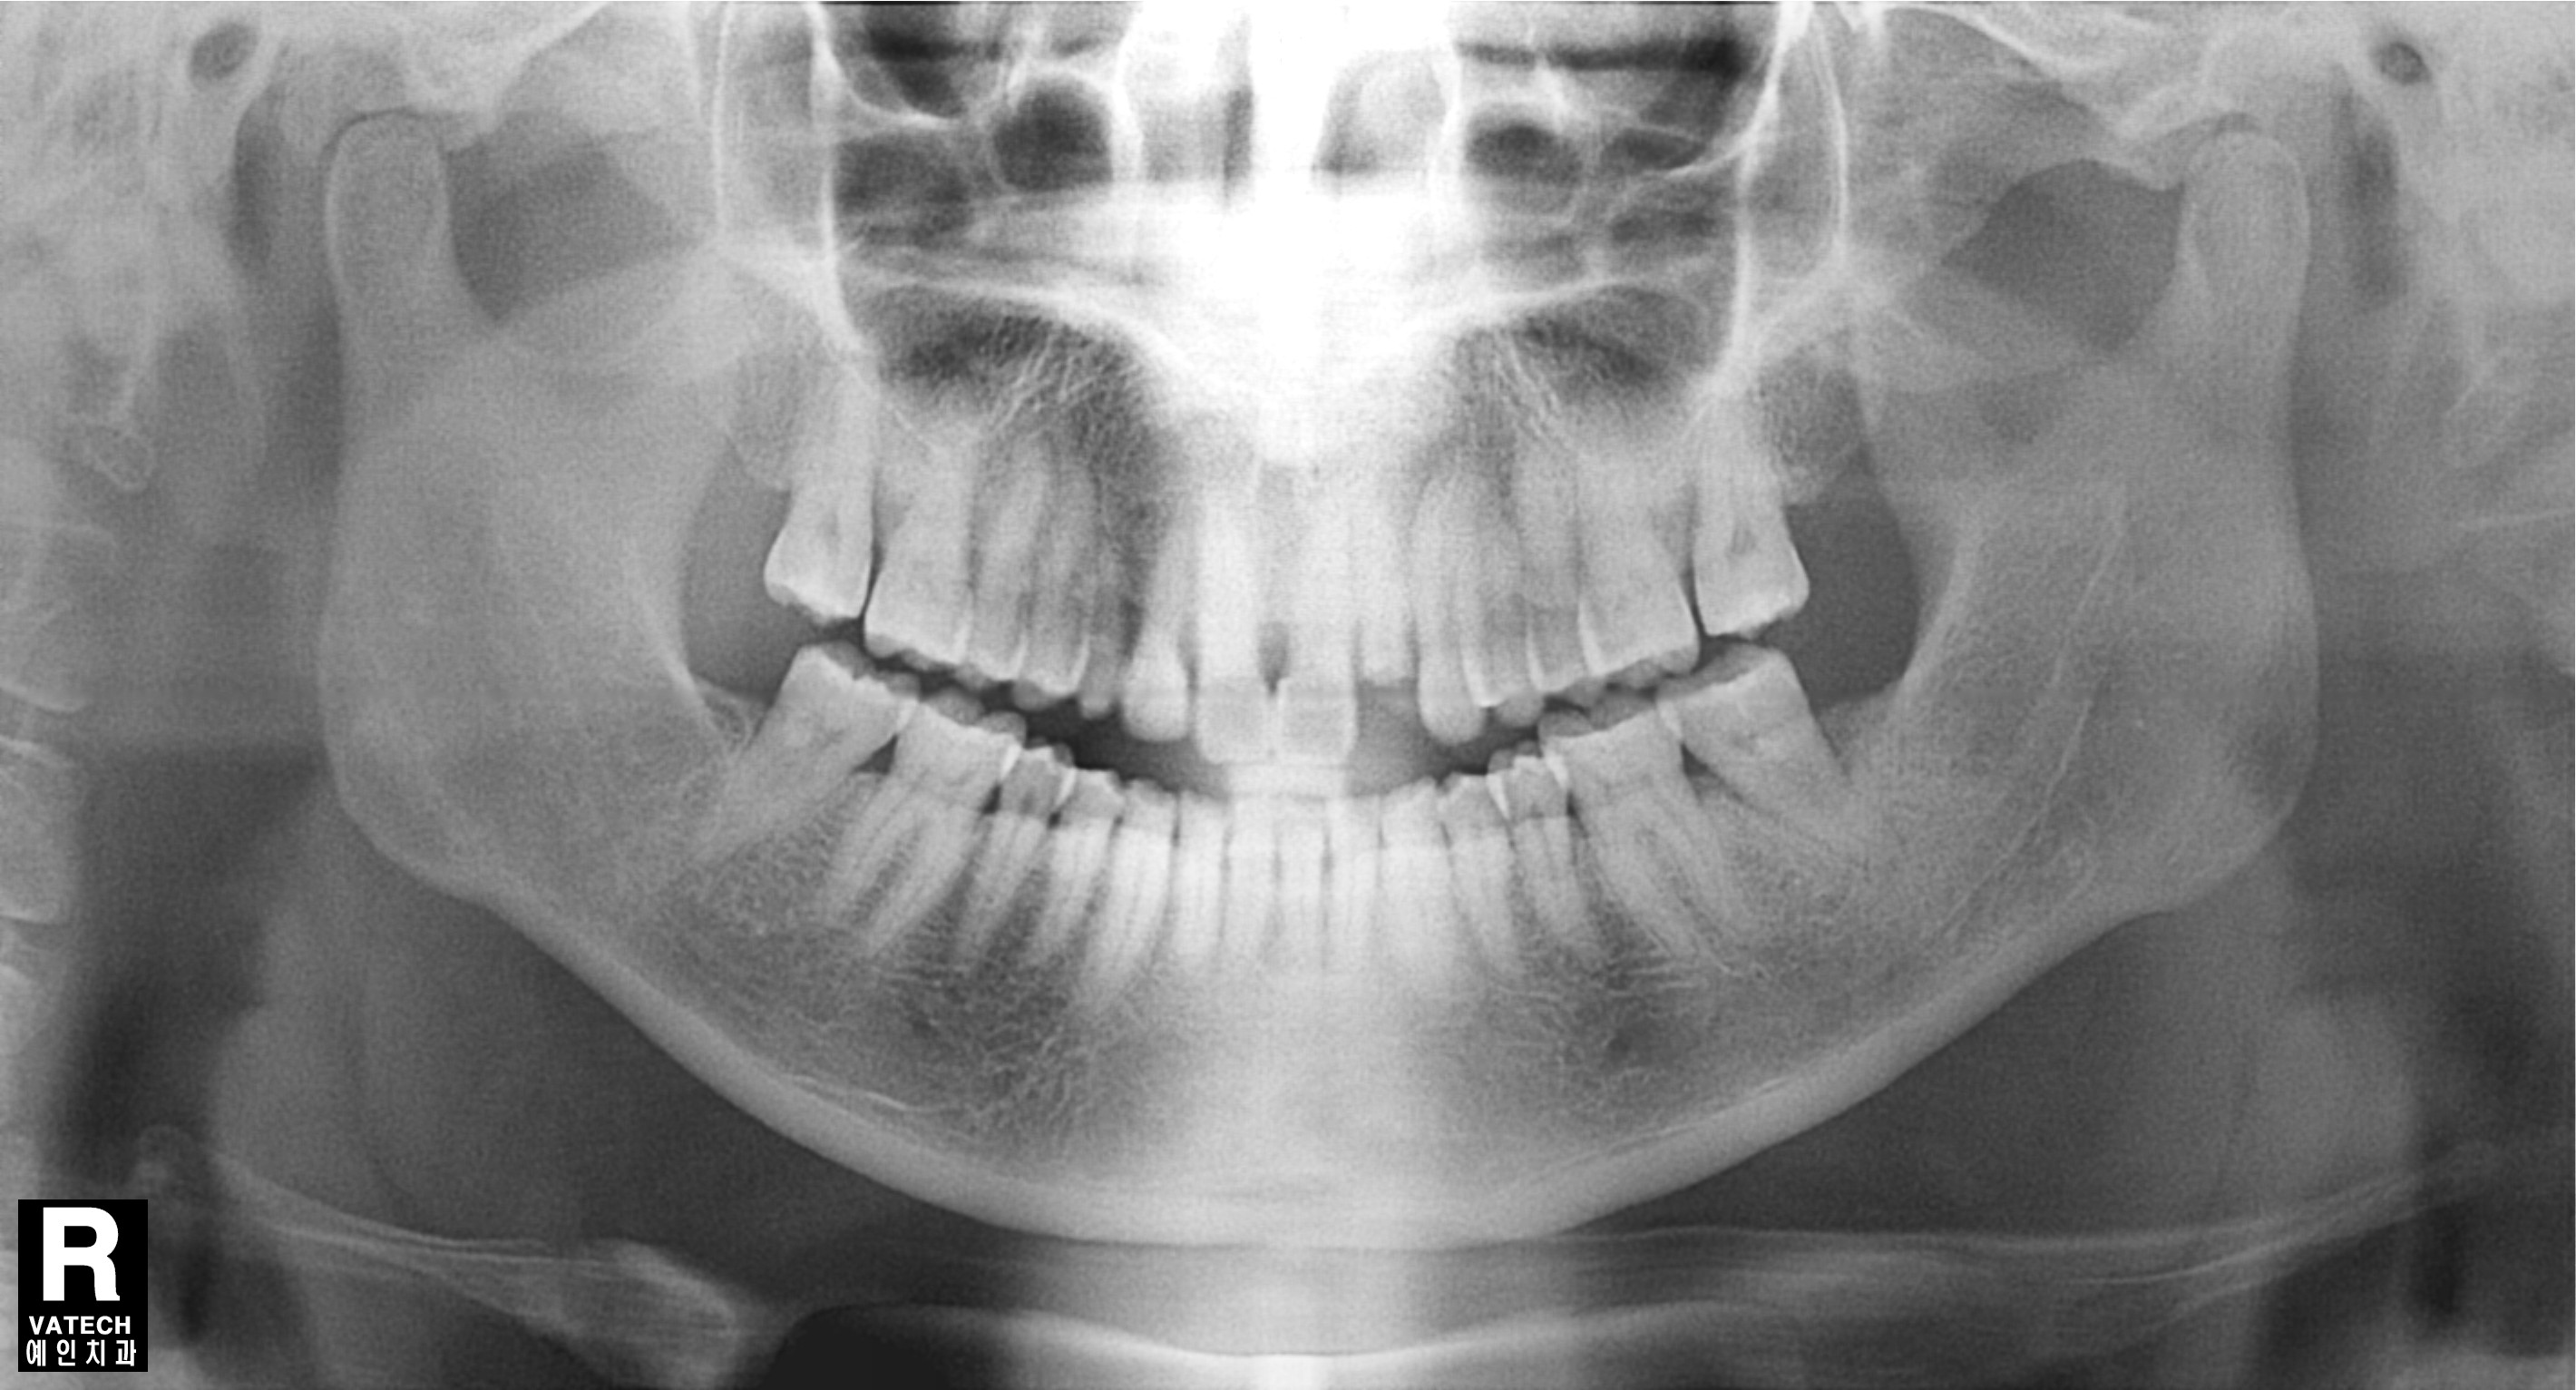

After

발치후 즉시 임플란트